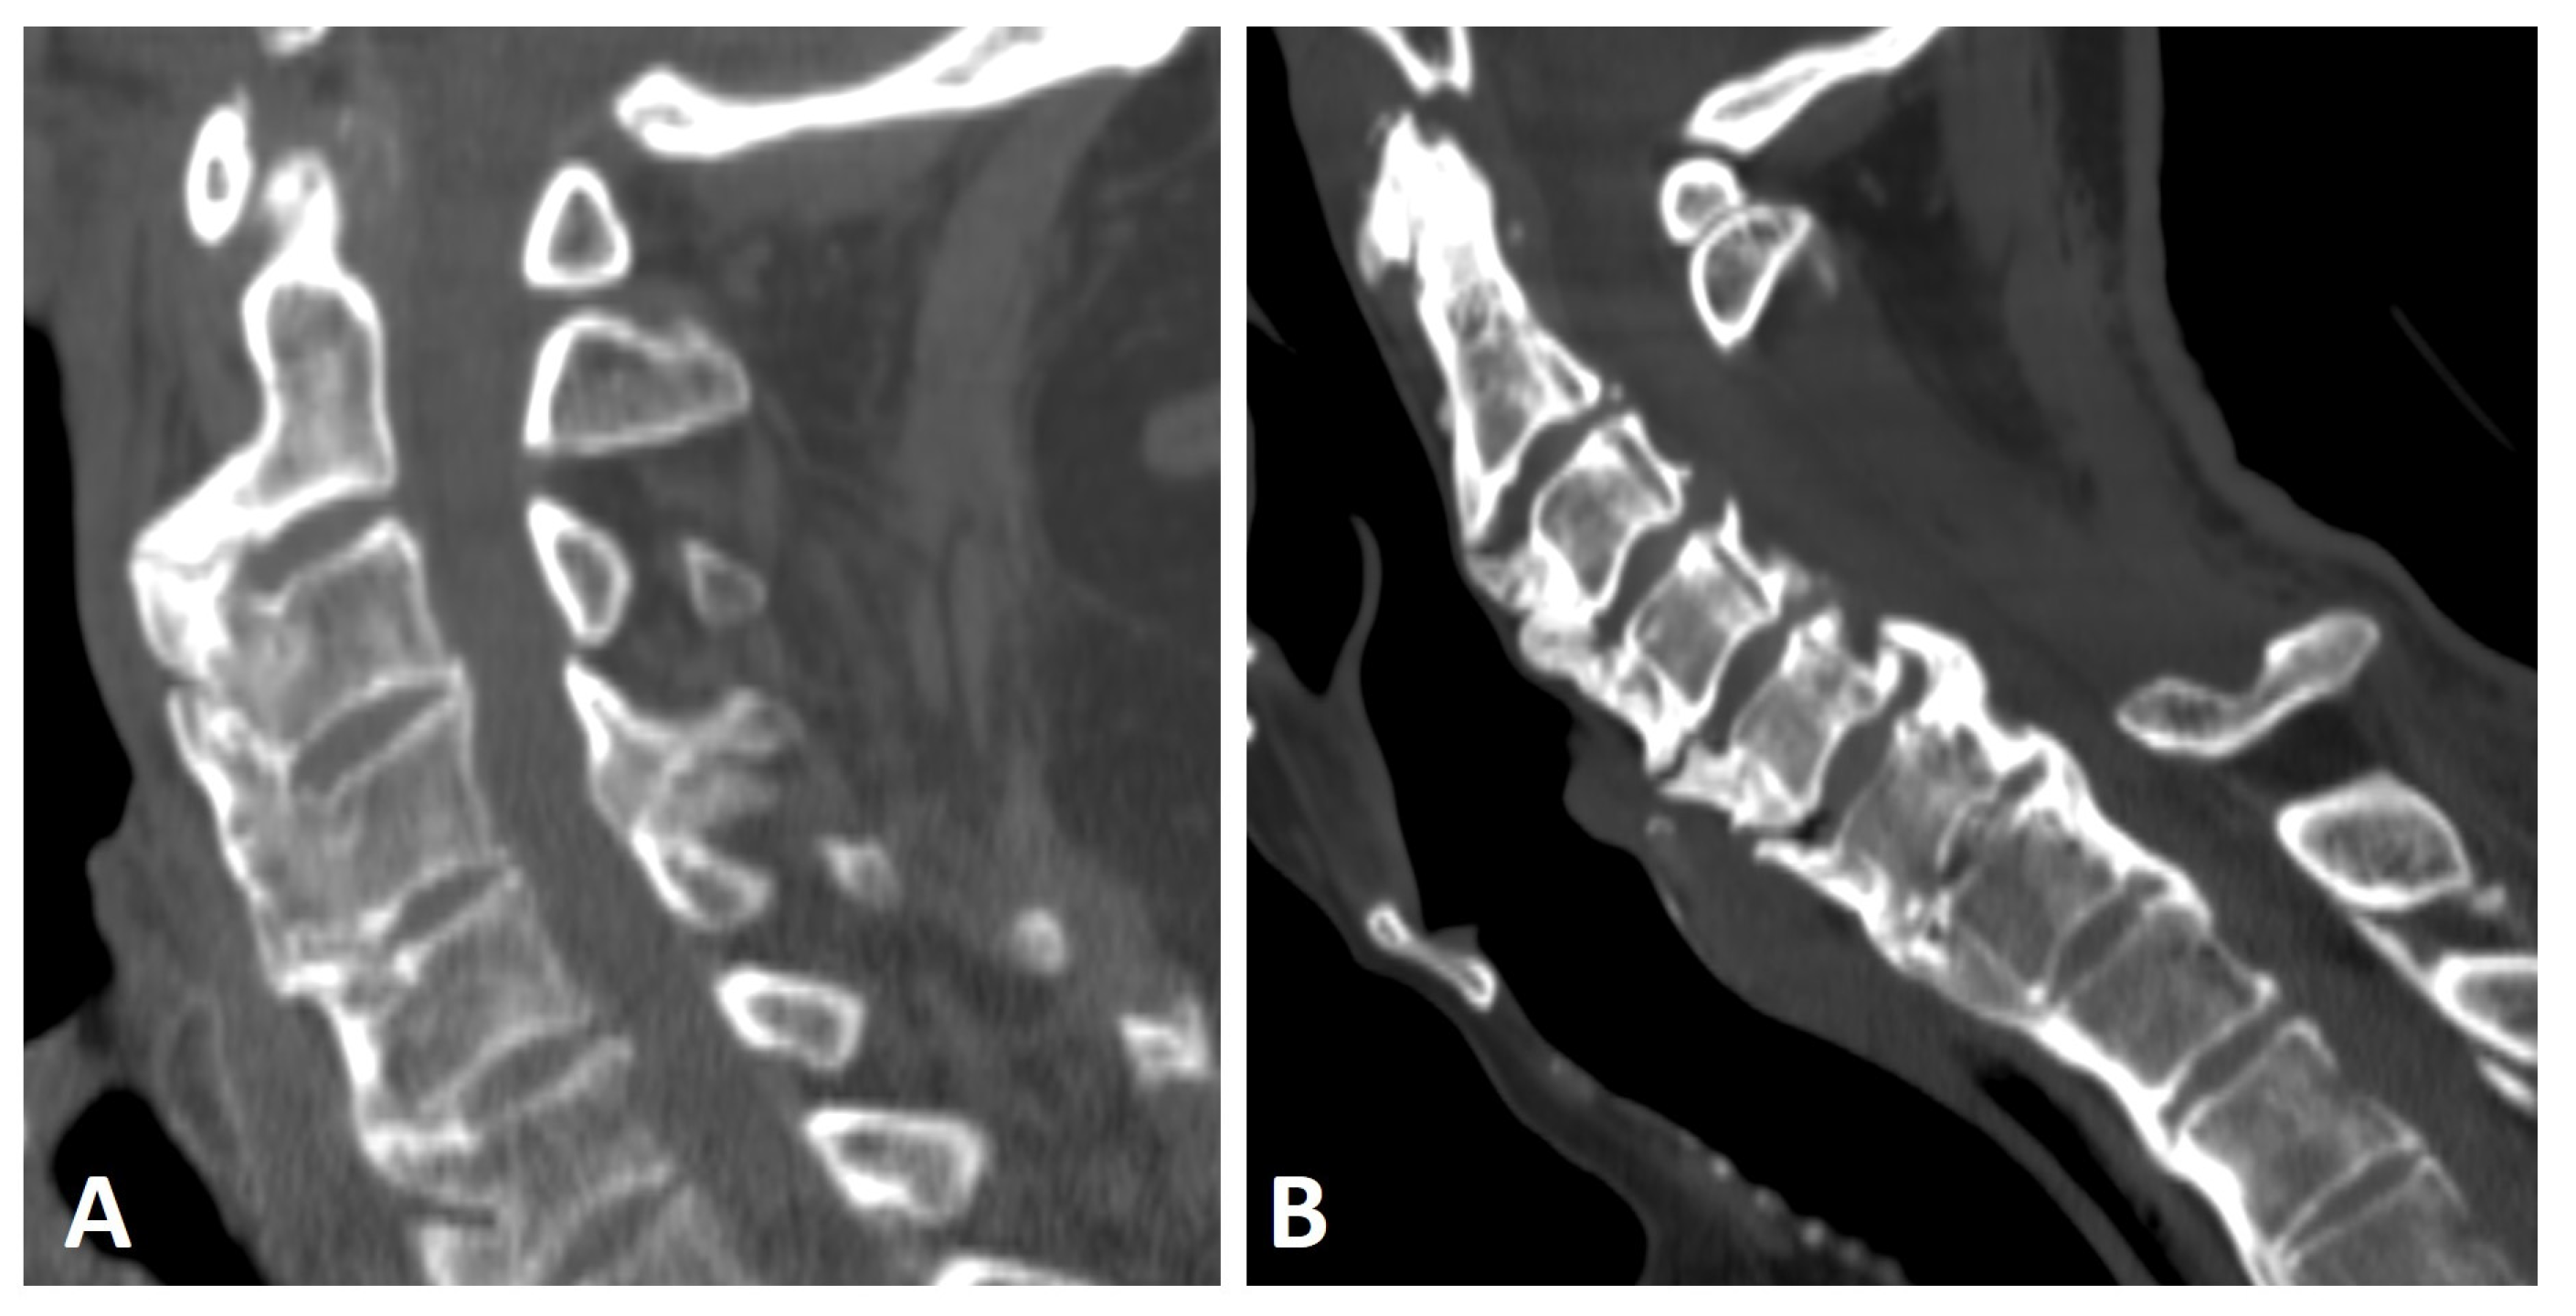

Anterior ossification of the spine in DISH may involve the cervical spine, primarily along the lower half of the anterior border of the vertebral body, forming a “candle flame” or “parrot-beak” image (Figure 2) [32]. These cervical flowing osteophytes are frequently asymptomatic but may result in dysphagia, sleep apnea, airway obstruction, and difficulty in intubation [7,23,33]. It has been reported that approximately one-third (33%) of subjects with DISH involving the middle or lower thoracic region have coexisting DISH in the cervical spine, according to whole-spine computed tomography (CT) [34].

Figure 2.

Sagittal CT reconstruction images of two patients with thoracic (not shown) and cervical DISH. (A) Flowing chunky osteophytes are located anteriorly to the vertebrae, forming a “candle flame” or “parrot-beak” image. (B) Thick, not-yet-flowing anterior osteophytes and thick posterior osteophytes at the C5–6 level.

In DISH subjects, bridging osteophytes in the cervical spine primarily occur anteriorly and are symmetrically distributed relative to the midline of the vertebral bodies [35]. In contrast, in the thoracic spine, osteophytes are typically asymmetrical and anterolaterally located [25,36]. It has been suggested that vascular structures act as a natural barrier for the formation of flowing osteophytes in the thoracic spine in DISH [25,29,36]. Thus, the different patterns of new bone formation between the cervical and thoracic spine may stem from differences in vascular anatomy.